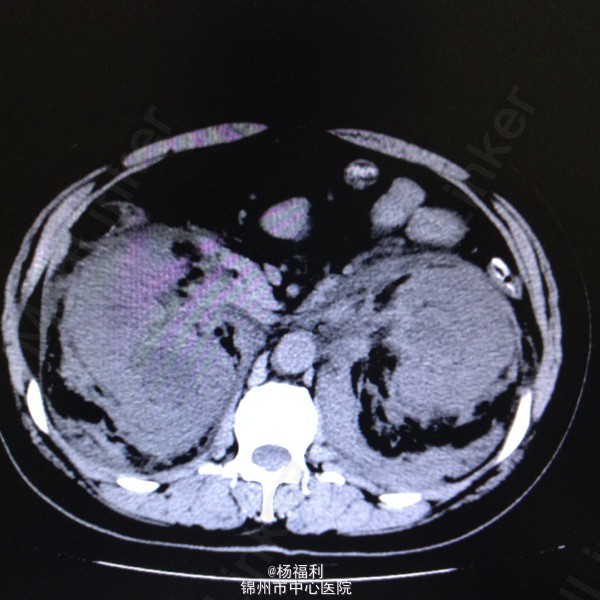

44岁女患。为消化科我会诊患者。 现病史:以上腹痛9小时为主诉入院。无发热及寒战、噁心未呕吐,无腹泻及黑便。 既往史:双眶炎性假瘤2年,口服激素治疗,并补钾。

查体:上腹部压痛,无反跳痛、右侧压痛明显,右肾区叩击痛,左肾区轻叩击痛,双输尿管走形区无压痛。 辅助检查;泌尿系彩超:双肾积水。 血白细胞:9.99*10^9。 肾功能正常。 全腹部ct及MRU检查:见图片。

诊断;真的不知道是啥病。 处理:暂时止痛处理。双肾病变。不知从哪里下手。